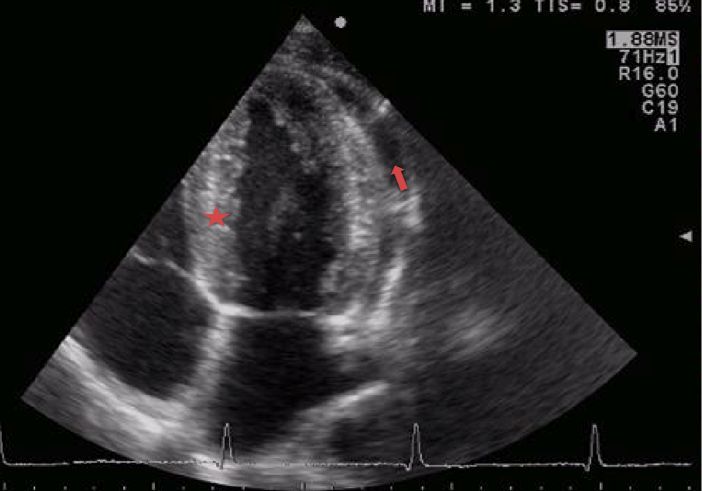

L�ecocardiografia ha messo in evidenza un versamento pericardico non rilevante emodinamicamente e una peri-miocardite (Figura 1 e Figura 2).

Figura 1. Ecocardiografia a riposo. Aspetto iperlucente del miocardio (stella), segno di miocardite, versamento pericardico (freccia).